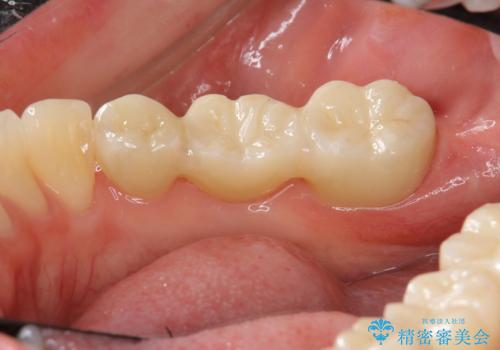

途中全体矯正をはさみ、根の向きが並行になった状態でブリッジを入れることができました。

- 36.3万円 (ジルコニアクラウン 10万円×3、仮歯1万円×3)費用は治療当時の料金となります